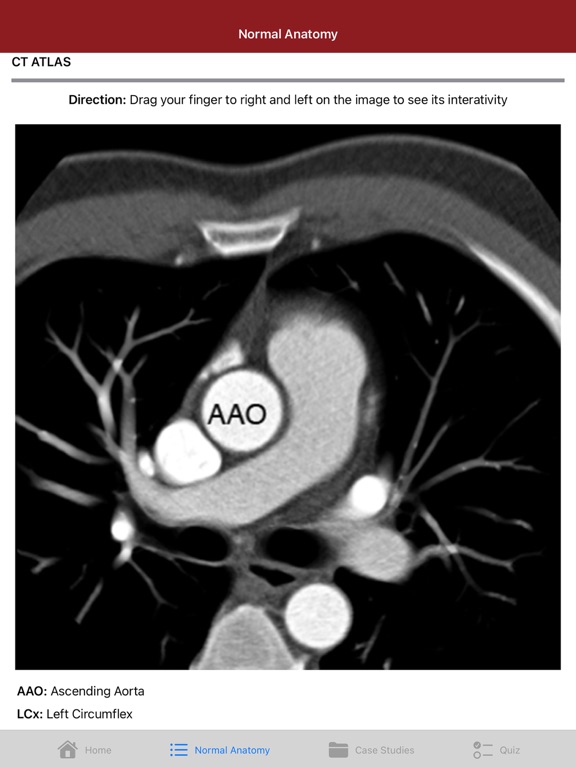

This educational app is designed to provide an organized approach to understanding coronary anomalies. It is intended for radiologists, cardiologists, and cardiac imaging staff at the trainee or practicing level. We have compiled a collection of figures, diagrams, case examples, and video discussions for the full multimedia discussion of coronary anomalies. We hope that this application provides a valuable resource for helping you learn and understand coronary anomalies.